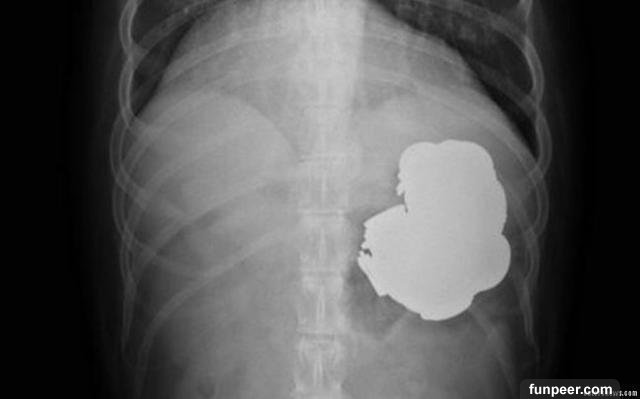

辛格的胃裡全部都是金屬類物質,大約有140枚金幣,150根針,還有一堆螺母,螺絲,還有廢舊電池……

醫生告訴家屬說,要是他不及時來就醫,這些針可能刺破他的胃,而導致死亡!

Gandeep戈亞爾博士和他的五人小組花了九個小時對辛格進行手術,但是因為他的身體承受能力有限,所以醫生第一次只能清除他胃裡大部分的金屬物質。下一個手術時間還在估量中……